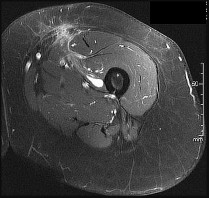

This patient has a dedifferentiated liposarcoma within a preexisting atypical lipomatous tumor. The imaging demonstrates a large fatty mass with increased internal septations proximally (the atypical lipomatous tumor) and a solid enhancing mass distally (the dedifferentiated portion). A biopsy reveals a high-grade liposarcoma. The other diagnostic responses do not reflect sarcomatous transformation of the lesion.

Surgical treatment of a high-grade sarcoma involves wide surgical resection. Radiation decreases local recurrence but does not clearly influence overall survival. The role of chemotherapy in high-grade soft-tissue sarcomas remains investigational; there is a modest (8%-15%) associated improvement in overall survival.

Intramuscular lipomas and atypical lipomatous tumors are treated with marginal resection alone. Radiation therapy for soft-tissue sarcomas may be given before or after surgery. When administered before surgery, patients have a higher wound complication rate but better long-term function attributable to lower rates of lymphedema, fibrosis, and contractures.